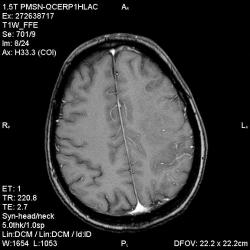

Из анамнеза - Женщина 45 лет. За год похудела на 15 кг (со слов матери), в последние месяцы случались эпизоды потери сознания. Онкозаболеваний и прочая в анамнезе нет. Сознание спутанное, из особенностей в анализах только подъем амилазы крови.

К сожалению, не владею методом КТ, но учитывая наличие неравномерного уплотнения в мозговых структурах с элементами очаговых "вкраплений", единственное, что приходит на ум - это рассеяный склероз. Хотелось бы уточнить, что беспокоило пациентку в течение последнего года кроме потери веса и эпизодов потери сознания? Была ли какая-либо очаговая неврологическая симптоматика? Отмечались ли какие-либо расстройства в двигательной или чувствительной сфере и т.д.? С уважением Helenmar.

И это точно не РС, т.к. характер очагов другой, ни один из них не копит контраст, нет субтенториальных очагов (извиняюсь, я этого в сообщении не указал), нет клиники.

"Раскрою" карты. Мы подумали о синдроме MELAS (mitochondrial encephalomyopathy, lactic acidosis and stroke) - дословно, митохондриальная энцефаломиелопатия, лактоацидоз и инсульт. В качестве дифференциальной диагностики можно было бы предположить вирусный энцефалит, но опять-таки, расположение очагов смущает - только с одной стороны и в абсолютно различных структурах.

В данном случае мы видим импульную последовательность FLAIR - режим с подавлением сигнала от воды, поэтому ликвор гипоинтенсивен, а также (вторая серия) - изображения, взвешенные по T1 после введения контрастного препарата. На T1 жидкость (ликвор) также представляется гипоинтенсивной. Зато на этих сериях гиперинтенсивны сосуды, т.к. контрастное вещество циркулирует в кровяном русле.

Что касается "белых" костей свода черепа, так это не кости, а кожа и подкожная клетчатка. Кости - глубже, "серовато-черные".

Изменения носят сосудистый характер. Процесс достаточно острый, имеется объемное воздействие, борозды левой гемисферы компремированы. По поводу MELAS синдрома очень сомневаюсь, почему поражена только левая гемисфера? Надо делать МР-ангиографию, смотреть нет ли стеноза

MELAS синдром - дебютирует с детских лет, характерен целый комплекс неврологических проявлений, заболевание генетическое, поражение системное, хотя есть множество вариантов митохондриального поражения, все же сомнительно. Хотелось бы акцентировать внимание, что гиперинтенсивные очаги есть в мозолистом теле, поражены выражено перивентрикулярные отделы, U -пути, белое вещество, поэтому так категорично демиелинизацию не вычеркивала бы из дифряда ( хотя тоже нетипично односторонее поражение). Думаю, для объективных выводов все же мало общей информации о пациентке, были ли клинические эпизоды раньше, чем объяснить такую потерю веса (возможно есть проявление паранеопластического синдрома?). Ну и МРТ-контроль в динамике, ангиография.

Да, неоднозначный случай. Точно не РС и не ОНМК. Я бы написала асимметричную лейкоэнцефалопатию неясного генеза. Можно было бы думать о лимфоме (полифокальное поражение, да еще мозолистое тело вроде бы задействовано (эх, сагиттальчики бы)). Но! Учитывая отсутствие накопления КВ.... Ну и надо исключать интоксикацию, всяческие аутоиммунные процессы (в т.ч. и васкулиты), сахарный диабет, ну и естественно наследственную патологию обменных процессов. УУУх! Вот.......

Имхо ишемический онмк в бассейне сма. Особенно показательны 5-й и 6-й файлы, отграничение как раз на границе бассейнов средней и перикаллёзной. Плюс одностороннее поражение.